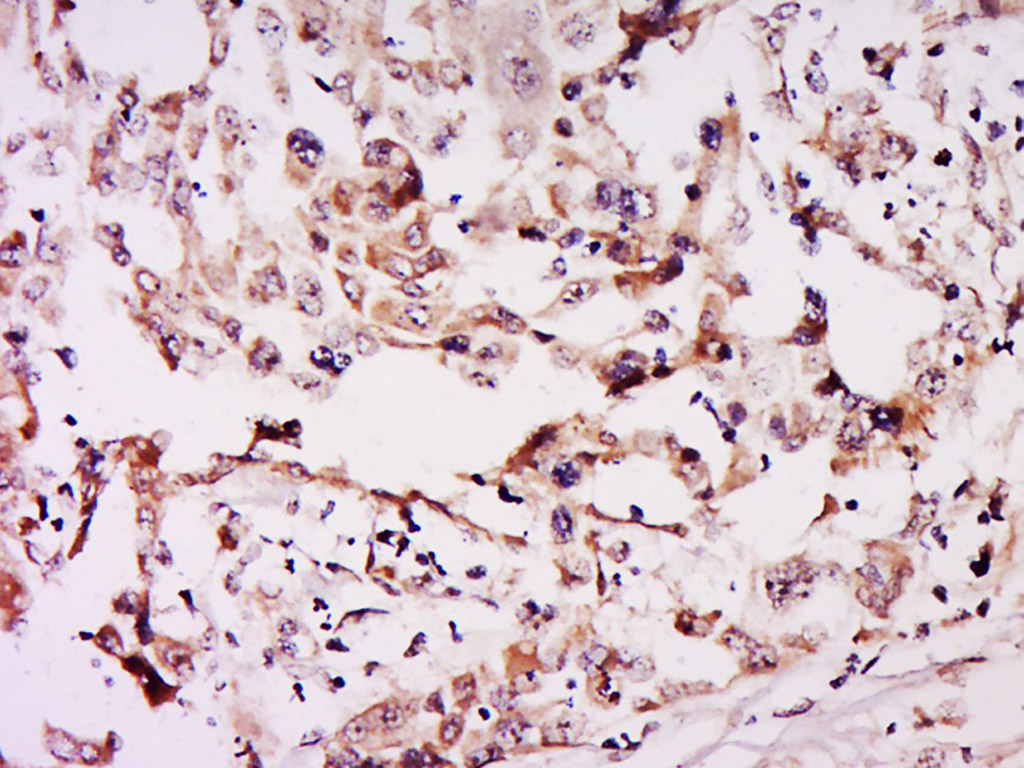

Tissue/cell: human breast cancer; 4% Paraformaldehyde-fixed and paraffin-embedded; Antigen retrieval: citrate buffer ( 0.01M, pH 6.0 ), Boiling bathing for 15min; Block endogenous peroxidase by 3% Hydrogen peroxide for 30min; Blocking buffer (normal goat serum,C-0005) at 37∩ for 20 min; Incubation: Anti-NSUN6 Polyclonal Antibody, Unconjugated(bs-19484R) 1:500, overnight at 4∑C, followed by conjugation to the secondary antibody(SP-0023) and DAB(C-0010) staining